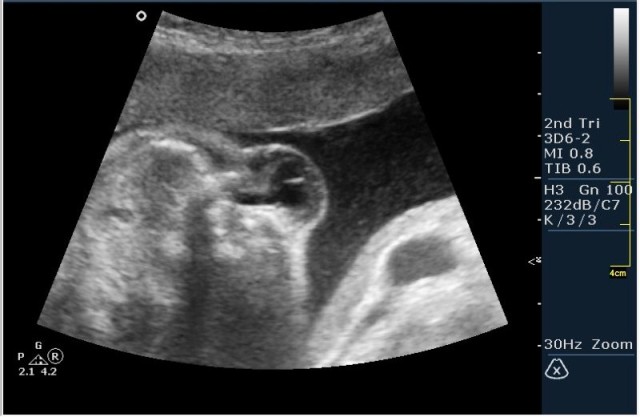

Женщина 23 года; из глухой деревни. К врачу обращалась один раз, когда забеременела. Дату последних месячных не помнит. Gravida 2, para 0. Направлена гинекологом для определения точного срока беременности и состояния плода.

Если нужна консультация-пожалуйста: Вы столкнулись с классическим случаем Spina Bifida Cystica.

Классические изменения при данной патологии таковы:

1.Вентрикуломегалия/гидроцефалия (на сонограмме №1 размер задних рогов боковых желудочков 16мм при норме до 10 мм включительно;

2.V-образное расщепление позвоночного столбы(рахисхизис)(на сонограмме №6 отчетливо виден дефект в поясничном отделе);

3.наличие дорсально расположенного содержимого спинномозгового канала(на сонограмме №7 видны мозговые оболочки).Это описывается как менингоцеле.

На сонограммах головы плода визуализаируется гифдроцефалия, патогенетически связанная со спинномозговой грыжей (менингомиелоцеле) представленная в 2D и 3D режимах. В режиме Skeleton не удалось получить "картинку презентационного качества", плод начал сильно вертется; но рекоммендация очень грамотная